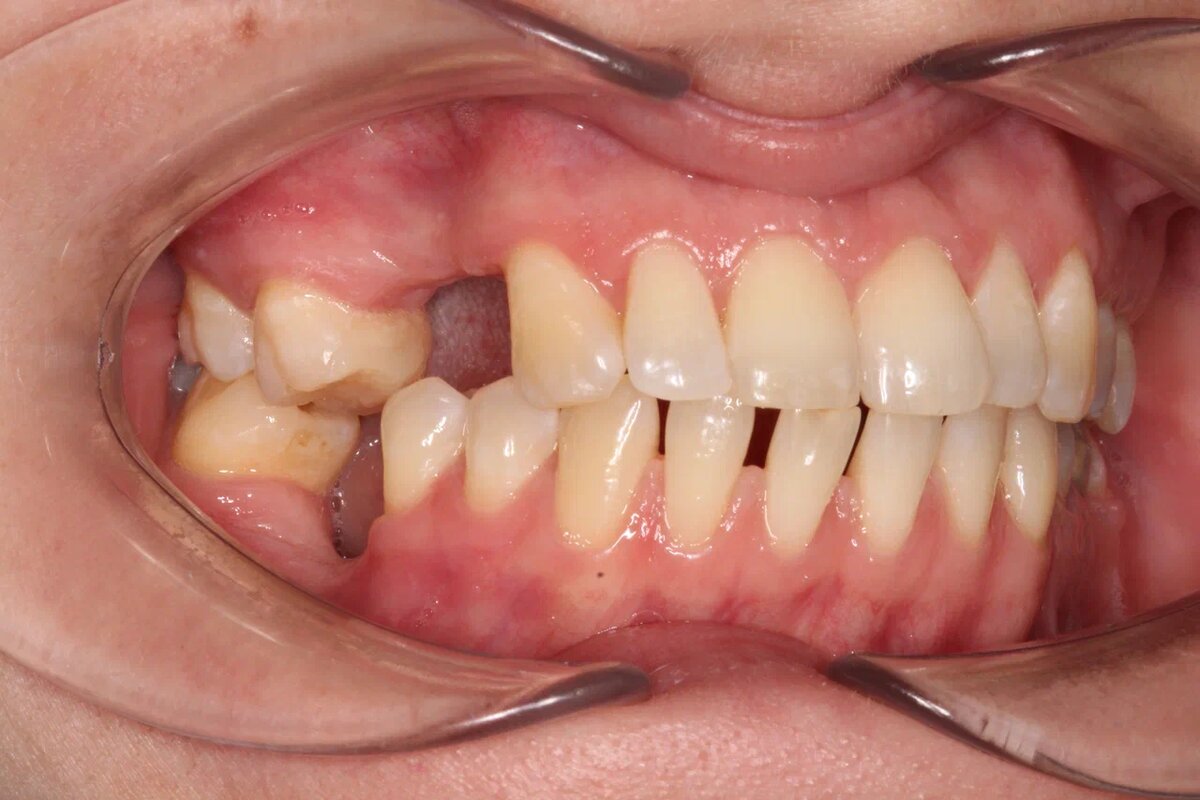

Начали в декабре 22-года терапевтически готовить рот к коррекции прикуса, по рекомендации ортодонта в марте 23-го удалили зубы мудрости и 1-го апреля зафиксировали брекет-систему. Начался наш путь от странного смыкания к здоровому и спасению зубов, которые были ненадежны по разным причинам.

Спустя полгода от начала ортодонтического лечения устанавливаем импланты справа вверху и сразу коронуем их временными реставрациями. Оздоровление прикуса продолжается, импланты в это время приживаются.